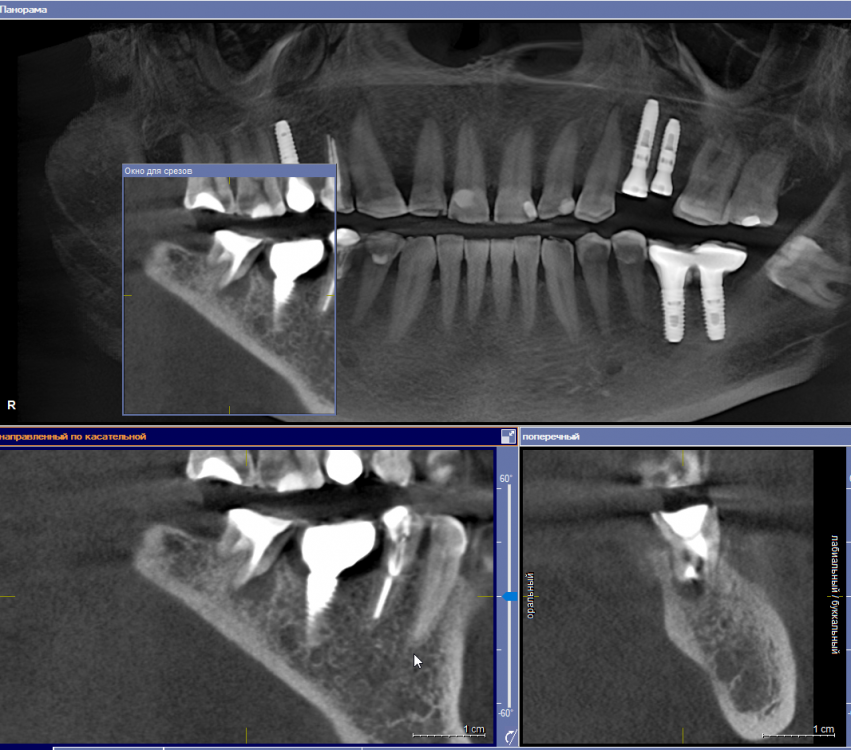

se77777 Опубликовано 19 сентября, 2022 Поделиться Опубликовано 19 сентября, 2022 Добрый день, 37. Эндодонтическое лечение с микроскопом 2,5 года назад. Слабая невнятная боль возвращалась от случая к случаю. Даже была тенденция к затягиванию полости. Но, похоже, не получилось. После коронавируса и серьезной нагрузки, впервые боль на короткое время обострилась. Полость, похоже, растет. От дна полости кисты до канала нерва 6 с небольшим мм. Показано ли в таком случае одномоментное удаление и имплантация? Спасибо. Ссылка на комментарий

red_butler Опубликовано 19 сентября, 2022 Поделиться Опубликовано 19 сентября, 2022 3 часа назад, se77777 сказал: Показано ли в таком случае одномоментное удаление и имплантация? Срезы не совсем корректные, но одномоментная имплантация скорее всего возможна 1 1 Ссылка на комментарий